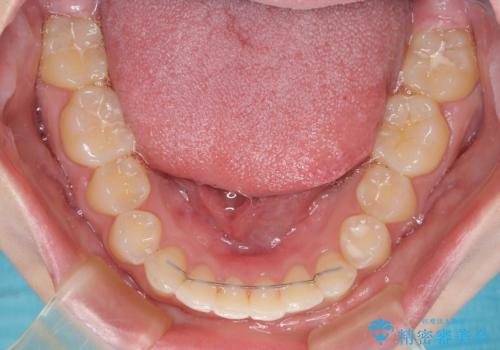

左上の歯列は補助装置により速やかに移動し、1年程度で奥歯の咬み合わせが改善され、1年3ヶ月の短期間でしっかりと仕上げることができました。